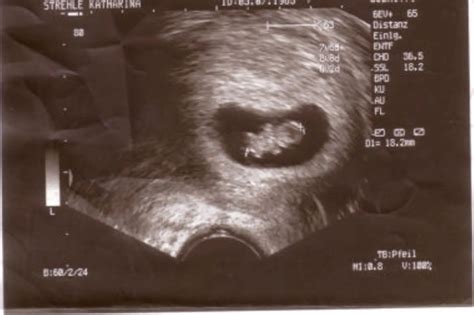

Die Keimscheibe entwickelt sich weiter und besteht nun aus drei Schichten, aus denen später in weiteren unzähligen Teilungsschritten sämtliche Organsysteme und Gewebe des Körpers entstehen. Im Laufe der sechsten Schwangerschaftswoche beginnen die ersten Organe, Form anzunehmen, und auch Kopf, Rumpf und Ansätze der Gliedmaßen sind erkennbar. Diese Woche stellt einen Meilenstein in der Entwicklung des Embryos dar: Das Herz beginnt zu schlagen und der Embryo bildet ein eigenes Kreislaufsystem aus. Der Embryo ist nun rund fünf Millimeter groß.

In der achten Schwangerschaftswoche ist der Embryo etwa 15 Millimeter groß. Neben dem Herz sind weitere Organe wie Nieren und Magen angelegt und beginnen zu arbeiten. Mit Mund, Nase und Augen beginnen nun auch die Sinnesorgane, sich zu entwickeln. Bei der Körperform des Embryos dominieren der Kopf und die oberen Extremitäten.